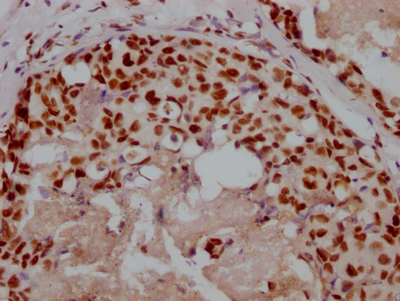

Immunohistochemistry of paraffin-embedded human gastric cancer using CSB-PA006593LA01HU at dilution of 1:100